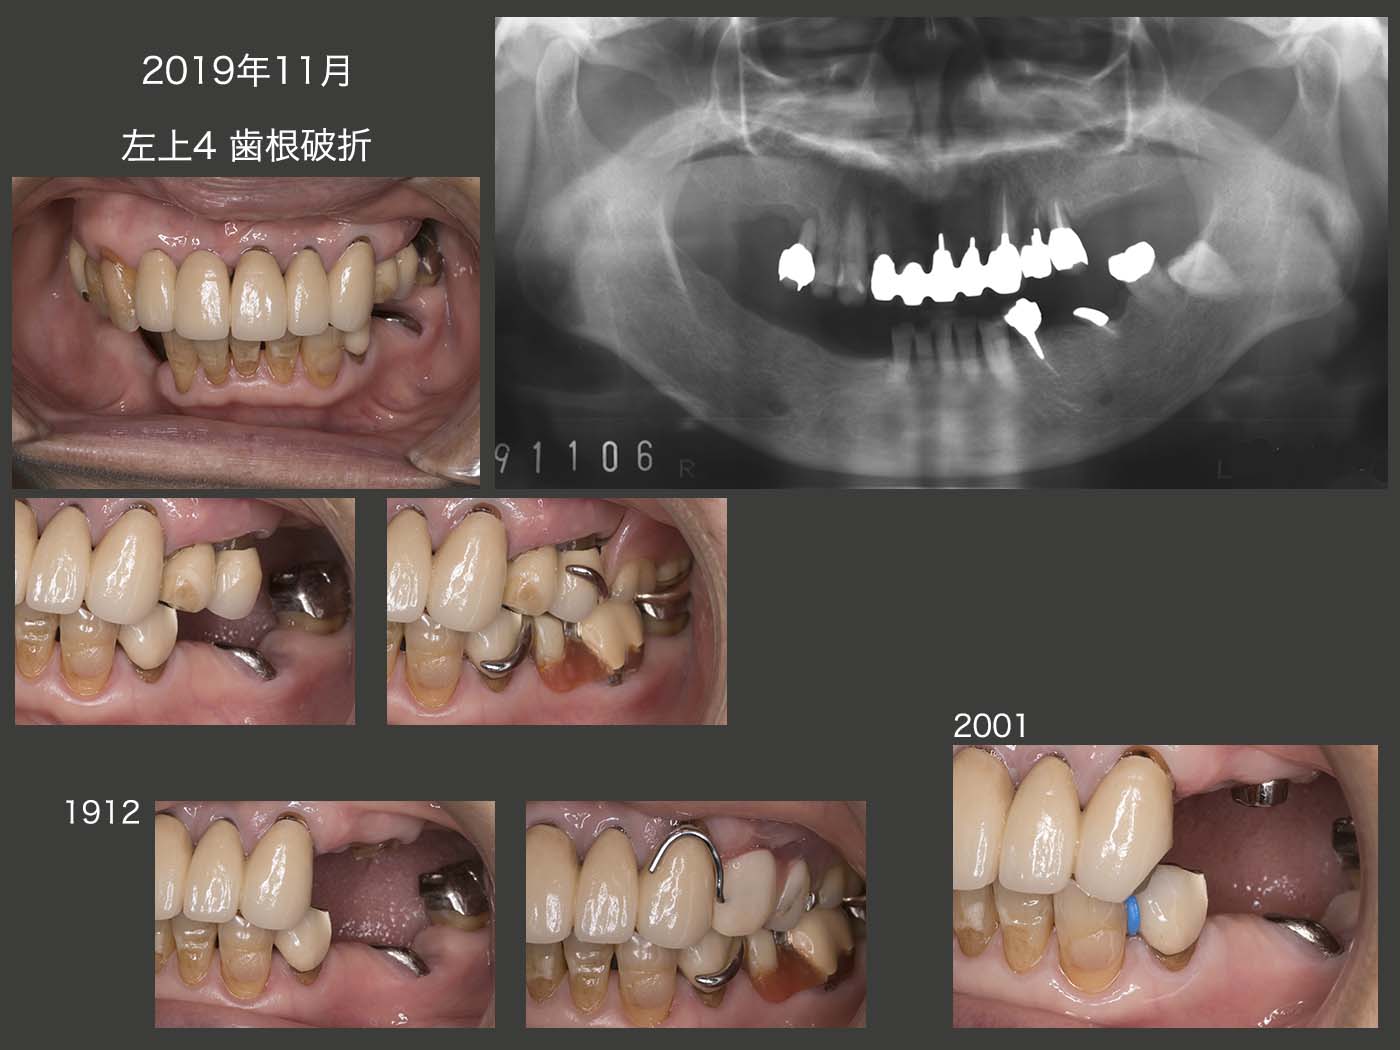

2014年3月,左上4のメタルボンド冠が破損し,コアとともに脱落した.同日,破損部を修理し,再合着した.15年11月,左上4のメタルボンド冠が再び破損した.17年8月,左下6の遠心根が歯根破折した.この歯は,近心側が左上5と咬合しているので,通常は近心根の破折を疑いたくなるが,実際は遠心根であった.左下7にクラスプを新製し,除去した左下6の冠を人工歯として,再利用した.

2017年11月,初診から15年2ヵ月,初診終了から13年8ヵ月後の状態.この間,初診時に抜歯した保存不可能な右下3を除き,11年に右上6,および17年に左下6の遠心根を失っただけであることから,経過は良好と言える.しかし,12年8月の右上5のデンタルX線写真からみてとれるように,支持歯槽骨がほとんど存在しない状態で,17年まで保っているということは,言い換えれば右側ではほとんど咀嚼していないことになる.11年に行った人工歯排列位置の改変は効果がなかったように思われる.なお,左上1,2の予後が心配であったが,特に問題は生じていない.

今後も,左側の咬合支持歯である左上3,4および左下4あたりが咀嚼の中心となることから,同部の歯に将来問題が生じる可能性が高い.

義歯装着時の状態.初診終了から約14年経っても,これほどレストの適合に変化がみられない症例はほとんど経験していない.このことは,咬合力が弱いことを意味するのか?もしくは,義歯ではまったく咀嚼せず,左側の咬合支持歯のみで咀嚼しているのかもしれない.

2019年11月,咬合支持歯である左上4に恐れていた歯根破折が生じ,遂に抜去せざるを得なかった.左上5は歯周ポケットが最大4mm,しかし動揺が著しかったので,根面板に変更した.

さて,このまま左側で咬むと,左上3と左下4の勝負になるが,左上3が負けて歯根破折が生じると,上顎前歯のブリッジ全体に影響を及ぼすことに繋がる.右上2の近心で切断することになり,一番避けなければいけない咬合形態である左右側すれ違い咬合に陥る.

そこで何としても左上3の歯根破折を阻止するために,対合歯である左下4を抜去し,左上4に移植する治療計画を立て,患者さんの了解を求めた.患者さんは,最初は了解して頂いたが,その後やはり左下4の抜歯はどうしても嫌であるとのことであった.その後,新型コロナの影響かあるいは私が左下4の移植を強く勧めたのが災いしたか,来院が途絶えている.